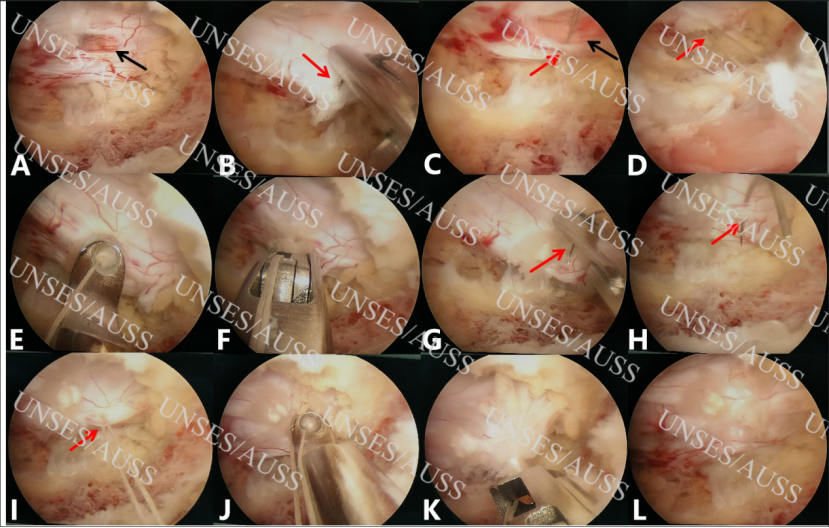

图4 UNSES/AUSS下硬膜囊缝合病例展示

图5 UNSES/AUSS下硬膜囊缝合病例展示

图6 UNSES/AUSS下硬膜囊双针缝合病例展示